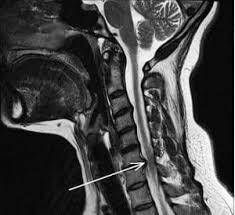

Betennelse i nakken kan oppstå grunnet flere årsaker. Det er svært vanlig å bli utsatt for betennelse i hælen med fysiske aktiviteter. Betennelse i nakken kan oppstå grunnet flere årsaker. Hvis lymfeknuden i nakken er betent, høyre eller venstre,i armhulen eller en annen del av kroppen, betyr det at kroppen står overfor en uvanlig tilstand og den beskyttende naturlige reaksjonen. Hvis du får nyrebekkenbetennelse, får du høy feber og kuldeskjelvinger. Den reaksjonen som skjer i vevet som følge av en akutt eller kronisk irritasjon, kalles betennelse eller inflammasjon. Du kan oppleve svie ved vannlating behandling av betennelse i prostata. Symptomene på betennelse i galleblæra vil vanligvis følge etter symptomer på gallestein. Betennelse eller inflammasjon (av latin īnflammō, «eg tenner», «setje fyr på») er ein del av dei komplekse biologiske responsane som blir sett i verk av vaskulære vev for å verne kroppen mot skadeleg stimuli, til dømes frå patogen, øydelagde celler eller irritasjonsmiddel. Han man vondt og en funksjonsnedsettelse (eksempelvis at man ikke kan løfte armen) har man i prinsipp de to vanligste symptomene på et funksjonsfeil, men bare to av fem tegn på betennelse. Frysninger og feber på mellom 39 og 40° c. Typiske symptomer ved betennelse i nakken er lokal hevelse, rødlig irritert hud og smerte ved trykk. Slike symptomer kan komme og gå i perioder og skyldes en irritasjon i pulpa, et hulrom midt inne i tannen fylt med nerver og blodkar.